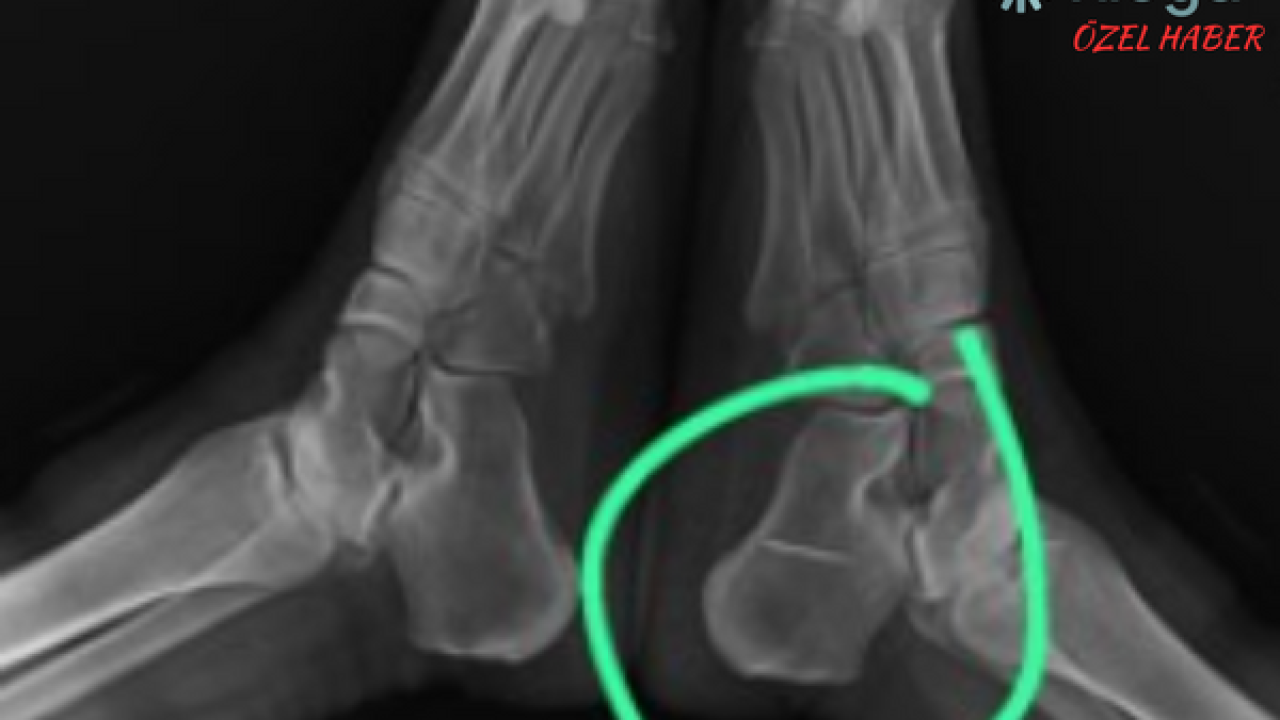

Röntgen sonucunu inceleyen doktor, Semra S'nin ayağının topuk kemiğindeki dikiş iğnesini görünce gözlerine inanamadı.

Hastasına bilgi vermesinin ardından, iğnenin kemiğe saplandığını ve hareket etmediği belirleyen acil servis hekimi, herhangi bir işlem yapılmasa da söz konusu iğnenin sorun yaratmayacağını iletti.